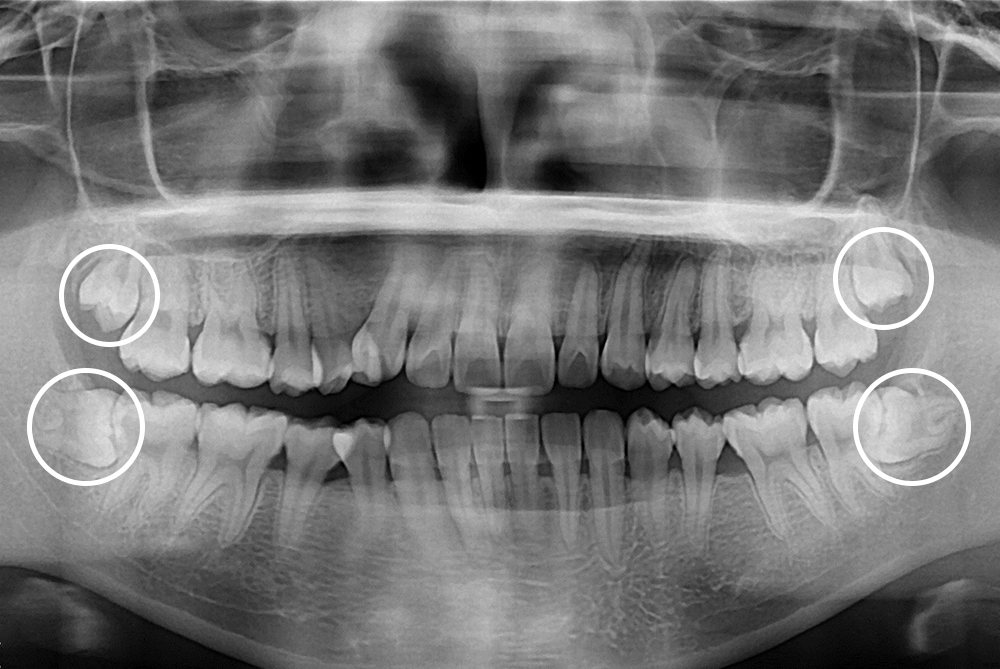

[사랑니] 매복 사랑니 발치

치료후 : 2021-03-22

세종치과는 구강악안면외과학 박사이신 원장님이 발치하는 치과입니다.